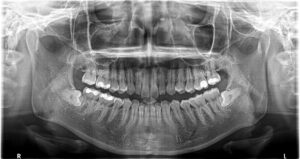

患者さんは20代女性。下の親知らずを抜いてほしいとのこと。

レントゲンを撮ると、左右親知らずが真横に埋まっています。

一般的にはこのような親知らずは大きな病院の口腔外科で行いますが、当院ではこのような親知らずにも対応しております。